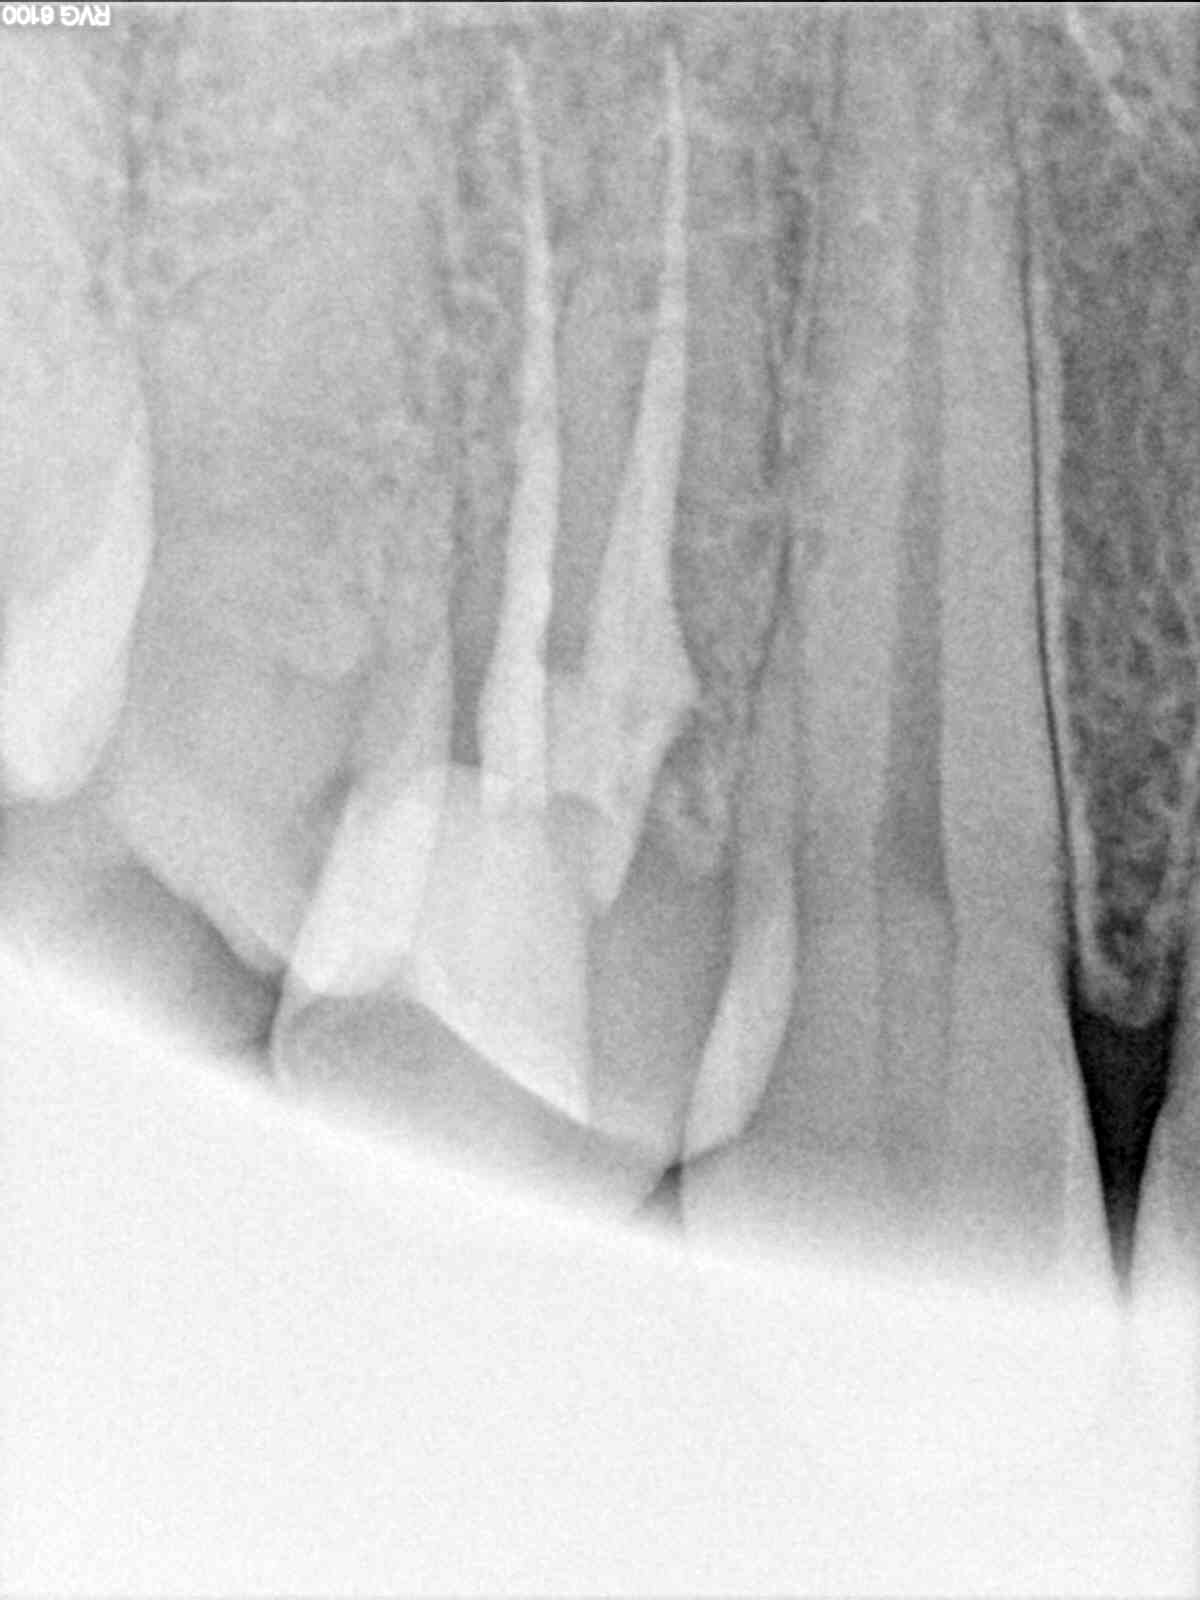

Heppp , on se calme ; aucun mépris la dedans , juste un peu d'humour pour désamorcer la discussion qui ne mène nulle part puisque nous ne serons jamais d'accord ! tiens une devinette toute fraîche (à l'instant ) et qui pourra alimenter votre parano de dentistes sous payés : où est l'endo faite en France ( par bibi ) pour 100 balles et celle faite au canada pour 600 ou 700 balles ? ( les 2 à 6 mois d'écart ) . Prix / qualité , on disait ? ( les prix sont arrondis pour les pointilleux qui scrutent la moindre erreur ...) . Et dire que les vendeurs de matos sont les mêmes pour ces 2 pays amis (!) , cherchez l'erreur ou tout simplement n'y aurait-il pas un peu d'abus par là ....